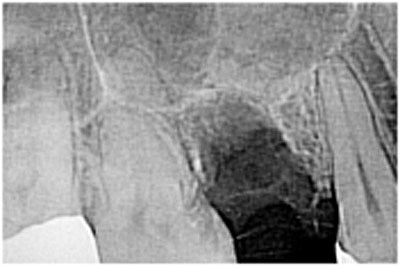

レントゲンをはじめCT沢山のデータより安全にインプラントを埋入しています。| |広島市安佐南区の歯科医院 レントゲンをはじめCT沢山のデータより安全にインプラントを埋入しています。 トップ お知らせ・ブログ レントゲンをはじめCT沢山のデータより安全にインプラントを埋入しています。 レントゲンをはじめCT沢山のデータより安全にインプラントを埋入しています。 Web診療予約 初めての方へ 選ばれ続ける理由 院内設備について 歯が痛いしみる一般歯科 歯がぐらぐらする歯周病 健康な歯を保ちたい予防歯科 子供の虫歯予防をしたい小児歯科 銀歯をセラミックに審美歯科 白い歯を目指しませんか?ホワイトニング 矯正専門医がいるので安心矯正歯科 抜けた歯を補いたいインプラント・入れ歯 医院案内 スタッフ紹介 メリィハウス歯科クリニックオフィシャルホームページ ラベンダー歯科クリニックオフィシャルホームページ お知らせ・ブログ ホーム 診療科目 一般歯科 歯周病治療 予防治療 小児歯科 審美治療 ホワイトニング 矯正歯科 入れ歯・インプラント マウスピース矯正 初めての方へ 院長・スタッフ 設備紹介 医院案内・アクセス メニューを閉じる